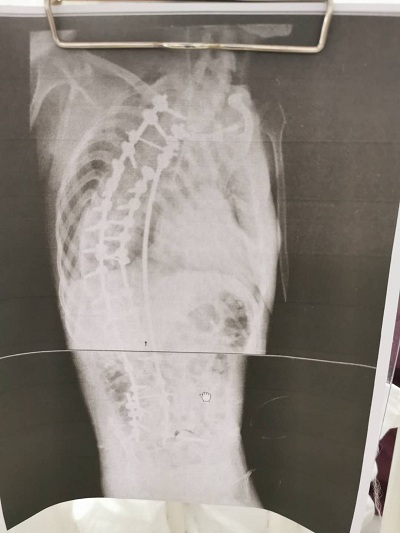

跑、跳这些最平常的动作,对于17岁的浙江大男孩小徐来说却是幻想,有时就连吃饭和呼吸都是一种奢侈。因患有罕见病脊髓性肌萎缩症,小徐脊椎严重弯曲,肌肉萎缩无力,大部分时间都只能躺在床上。即便如此,小徐一直没有放弃治疗,热爱生命的他用坚强的意志打动了很多人。

近日,小徐在上海交通大学医学院附属新华医院脊柱中心接受了脊柱矫形手术,穿上了“螺钉护甲”,身体外观和生命质量都大为改观,被疾病严重扭曲的身体一夜变直。小徐说,“命运对我虽然残酷,但我不会放弃任何希望,坚强生活。如果有余力的话,我还想帮助更多的人!”

长到17岁的小徐,身形弯曲,大部分时间都只能像蛇一样匍匐躺在床上,还常常呼吸困难,轻微的肺部感染就有发生呼吸衰竭的可能,甚至有生命危险。即便如此坎坷,但小徐始终不放弃求生的信念。

但脊髓性肌萎缩也不是完全没有治疗方法。SMA的手术治疗方式是从胸骨到骶骨的一个全脊柱固定,会使身体外观有明显改变。手术治疗可以阻止畸形进展、保持坐位躯干平衡,维持胸廓高度、维持肺功能,提高总体生命质量。在中国,能完成此种高难度手术的医院屈指可数,仅一两家医院可以治疗。

小徐因为神经肌肉萎缩,极重度侧弯,如果进行手术,术后极其容易出现呼吸衰竭。面对如此大风险的高难度手术,小徐的心肺功能是否能够耐受?术后会不会呼吸机拔管失败?

7月8日当天,新华医院杨军林教授的团队仅用了5个小时就完成了这样一例极重度的脊柱矫形手术,术中输血很少,一枚一枚的螺钉置入了身体中,犹如一件“螺钉护甲”,将小徐的脊椎托了起来,小徐蛇形的身体变直了。术后,小徐进入了监护室进行观察,各项生命体征都很平稳,当晚就拔除了气管插管进行自主呼吸了。专家透露,如果小徐恢复顺利,他身体外观和生命质量都将大为改观。